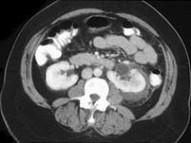

问题 男,48岁,有外伤史,请根据所示图像,选择最可能诊断 ( )

选项 A、左侧肾盂输尿管交界处撕脱伤 B、未见异常 C、左肾裂伤 D、左肾动脉撕裂伤 E、左肾挫伤

答案 C